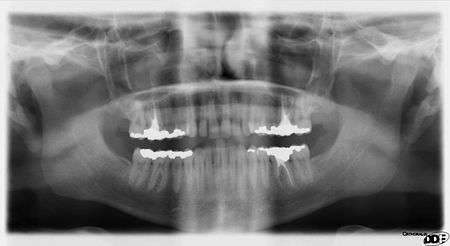

Dental Radiographs are commonly called x-rays. Dentists use radiographs for many reasons: to find hidden dental structures, malignant or benign masses, bone loss, and cavities.

A radiographic image is formed by a controlled burst of X-ray radiation which penetrates oral structures at different levels, depending on varying anatomical densities, before striking the film or sensor. Teeth appear lighter because less radiation penetrates them to reach the film. Dental caries, infections and other changes in the bone density, and the periodontal ligament, appear darker because X-rays readily penetrate these less dense structures. Dental restorations (fillings, crowns) may appear lighter or darker, depending on the density of the material.

It is possible for both tooth decay and periodontal disease to be missed during a clinical exam, and radiographic evaluation of the dental and periodontal tissues is a critical segment of the comprehensive oral examination. The photographic montage at right depicts a situation in which extensive decay had been overlooked by a number of dentists prior to radiographic evaluation